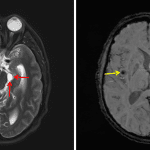

- Global ventriculomegaly with asymmetric enlargement of the left lateral ventricle

- FLAIR signal hyperintensity in bilateral parietal and occipital sulci

- Multiple small, rounded T2 hyperintense lesions involving the brain parenchyma and subarachnoid spaces with largest lesions in the right subinsular region, ventral left thalamus, left perimesencephalic cistern, and within the bilateral sylvian fissures. A few of these lesions have peripheral enhancement and a few have associated susceptibility artifact

- Neurocysticercosis

Global ventriculomegaly concerning for communicating hydrocephalus. Asymmetric enlargement of the left lateral ventricle could represent a component of superimposed obstructive hydrocephalus, though an obstructing lesion is not identified at the left Foramen of Monro.

Multiple small, rounded T2 hyperintense lesions involving the brain parenchyma and subarachnoid spaces a few of which have associated peripheral enhancement and susceptibility artifact. This appearance is most typical for neurocysticercosis.

FLAIR signal hyperintensity in bilateral parietal and occipital sulci may represent meningitis related to neurocysticercosis, though there is no accompanying leptomeningeal enhancement.